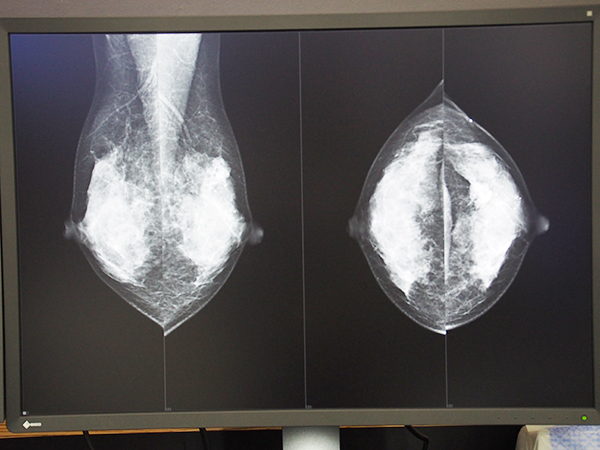

ネットカムシステムズは,ストレスのない,快適なマンモグラフィの読影環境を追究した乳腺画像診断ワークステーション「mammodite(マンモディーテ)」を4台設置し,来場者に軽快な操作性や高速な画像表示を体感してもらう展示を行った。

2012年に発売されたmammoditeは,リリース後も現場からの声を開発に反映し,常に進化し続けている。トモシンセシスの臨床導入も進みつつあり,マンモグラフィのデータ容量はますます大きくなっているが,これをスピーディに表示し,ストレスなく読影できる環境を追究するため,mammoditeでは統合プロセスエンジン“APROS”を独自に開発している。ここ2年ほどはバックグラウンドの開発強化を進めており,より安定的に稼働するようになっている。また,表示スピードだけでなく,直感的な操作性も重視しており,マニュアルがなくても使えるようなわかりやすいユーザーインターフェイスを実装。ワンタッチレイアウトや腫瘤計測,図形オブジェクト機能などを搭載し,効率的な読影をサポートする。

データ容量の大きいトモシンセシス画像も高速に表示可能